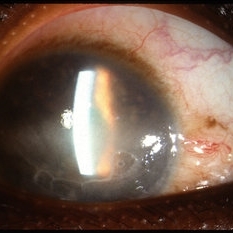

Sarcoid Bussaca Iris Nodules

Oct 11 2012 by Jeffrey G. Gross, MD, FASRS

Sarcoid bussaca iris nodules, with corneal edema.

Condition/keywords: autoimmunity, corneal edema, sarcoid bussaca iris nodules, sarcoidosis